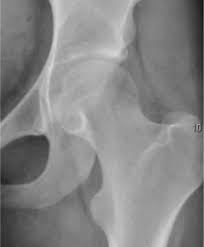

움직일 때 심해지는 통증

고관절 통증의 특징 중 하나는 특정 동작에서 통증이 더 뚜렷해진다는 점입니다.

• 앉았다 일어날 때 통증 발생

• 계단을 오르내릴 때 통증

• 다리를 벌리거나 꼬을 때 통증

• 오래 걸은 뒤 통증 악화

이러한 증상은 관절 자체의 문제이거나 주변 근육과 인대에 부담이 누적되었을 때 자주 나타납니다.